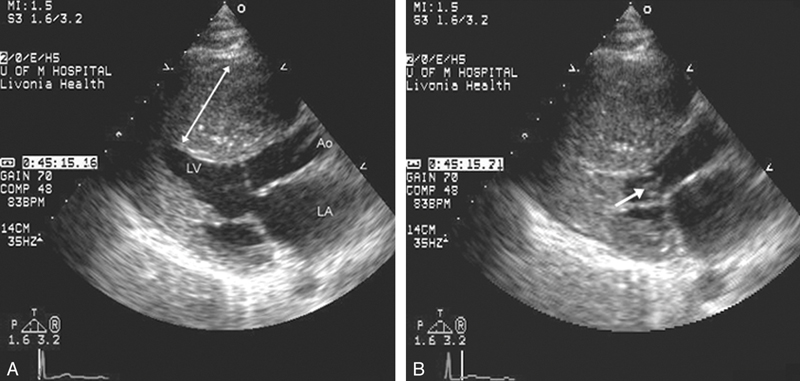

فحوصات تشخيصية لبعض امراض القلب والشرايين التاجية